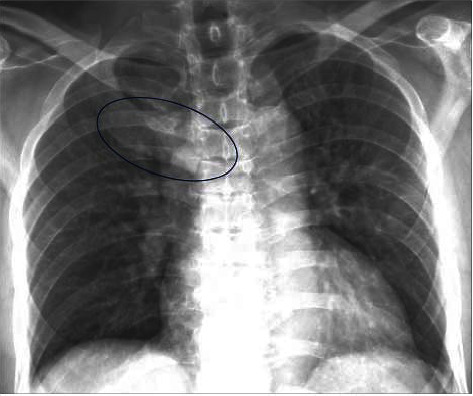

SAPHO综合征是一种罕见的骨、关节和皮肤炎症性疾病,因出现滑膜炎、痤疮、脓疱病、骨质增生和骨炎而得名。SAPHO综合征的标志包括骨关节和皮肤表现,然而,与炎症性肠病(特别是克罗恩病)的罕见关联已被记录。关于SAPHO综合征与炎症性肠病(IBD),特别是溃疡性结肠炎(UC)之间关系的文献仍然有限。我们报告一个不寻常的病例SAPHO综合征患者UC。胸部x线及MRI显示右侧第一肋骨及邻近胸骨肿大。骨显像显示肋软骨连接处骨质增生和强直,骨活检显示骨和肋软骨反应性,未见感染或恶性肿瘤。使用唑来膦酸4个月后症状完全缓解,无明显不良反应。SAPHO综合征在IBD患者中诊断罕见,在UC患者中更是如此,这可能是由于SAPHO综合征的临床异质性以及与IBD的肠外表现重叠导致的漏诊。我们的治疗方法为UC中SAPHO综合征的诊断和治疗文献提供了重要的数据。

SAPHO syndrome, a rare inflammatory disorder of bone, joints, and skin, is named based on the presence of synovitis, acne, pustulosis, hyperostosis, and osteitis. The hallmark of SAPHO syndrome includes osteoarticular and dermatologic manifestations, however, rarer associations with inflammatory bowel disease (particularly Crohn's disease) have been documented. The literature on the relationship between SAPHO syndrome and inflammatory bowel disease (IBD), especially ulcerative colitis (UC), remains limited. We report an unusual case of SAPHO syndrome in a patient with UC. Chest x-ray and MRI showed enlargement of the right first rib and adjacent sternum. Bone scintigraphy revealed hyperostosis and ankylosis of the costochondral junction, and bone biopsy revealed reactive bone and costal cartilage without findings of infection or malignancy. Complete resolution of symptoms was achieved 4 months after starting zoledronic acid without significant adverse events. The diagnosis of SAPHO syndrome in IBD patients is rare, even more so in UC patients, likely attributable to underdiagnosis given the clinical heterogeneity of SAPHO syndrome and overlap with the extra-intestinal manifestation of IBD. Our treatment approach provides critical data to the underreported literature on diagnosis and managing SAPHO syndrome in UC.